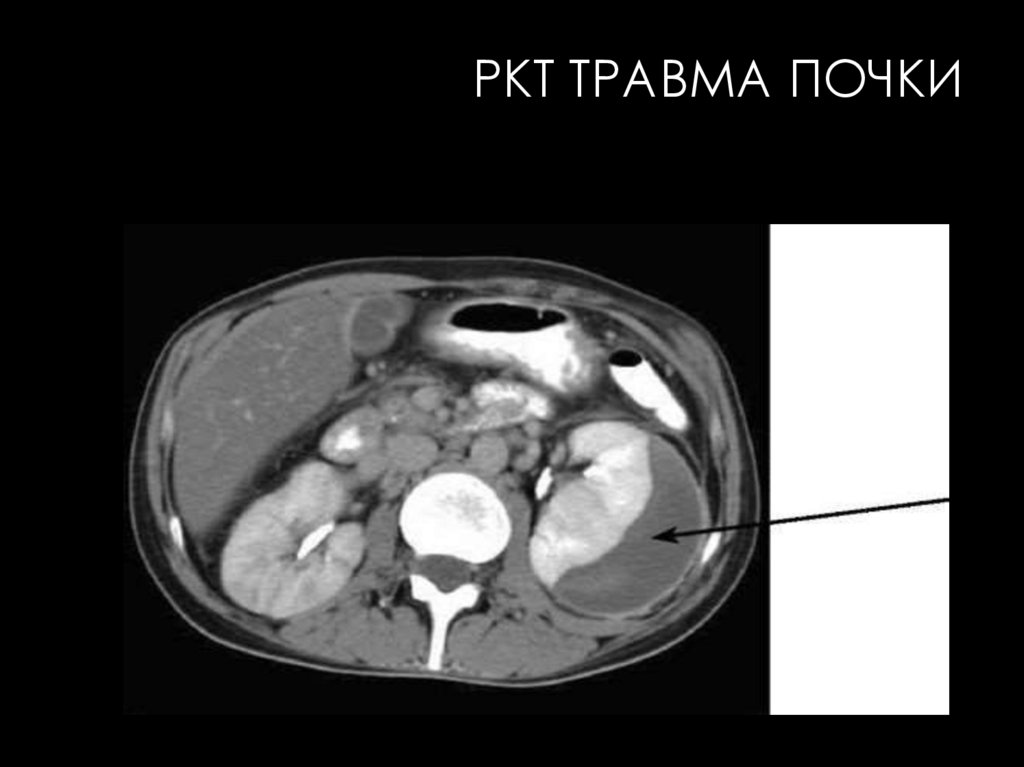

РКТ ТРАВМА ПОЧКИ

РЕНТГЕНОВСКАЯ КОМПЬЮТЕРНАЯ

ТОМОГРАФИЯ

КТ в урологической практике широко используется главным

образом для исследования почек

КТ-изображение почек в норме всегда отчетливое даже при

нативном исследовании, что обусловлено большой разницей

рентгеновской плотности самих почек (+30... +40 HU) и окружающей

их жировой клетчатки (-70... - 130 HU). Разница плотностей

обеспечивает также дифференцирование изображения почек на

паренхиму и почечный синус, тоже содержащий жировую клетчатку